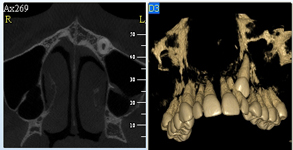

3D DVT - NewTom

Je speciální zubní digitální tříprostorový tomograf (3D), který umožňuje na základě jediného

snímkování vytvořit všechny typy RTG zobrazení, které jsou pro lékaře potřebné. Díky používané technologii tzv. „kuželového paprsku“ a speciálním senzorům je

výrazně zmenšená dávka záření - o více jak 80% proti klasickému CT vyšetření. To je významné zejména u dětí. Pomocí tohoto přístroje je možné zjisti skutečnou situaci v čelistních kostech pacienta tedy množství kosti - můžeme změřit skutečnou šířku i výšku kosti, i kvalitu kosti (hustotu) v místě uvažované implantace. 3D (tříprostorové) zobrazení umožňuje zvýšit prostorovou představu operatéra ještě před vlastní operací a zároveň pacientovi lépe objasnit a ukázat oblast plánovaného zavedení implantátu.

Pacient „neumí číst“ RTG snímky, ale díky 3D zobrazení vidí „svoji skutečnou čelist“

- např. jak je nízká či úzká, vidí průběh nervu nebo velikost čelistní dutiny, což mu umožní i pochopení nutnosti v některých případech provést pomocné zákroky ještě před vlastním zavedením implantátu (viz. kostní štěp, sinus lift, kostní granulát...).

Vyšetření pomocí tohoto přístroje používáme i ve stomatochirurgii (zlomeniny čelistí, zuby moudrosti, cysty, onemocnění čelistního kloubu), ortodoncii (retinované zuby, nadpočetné zuby), parodontologii atd.